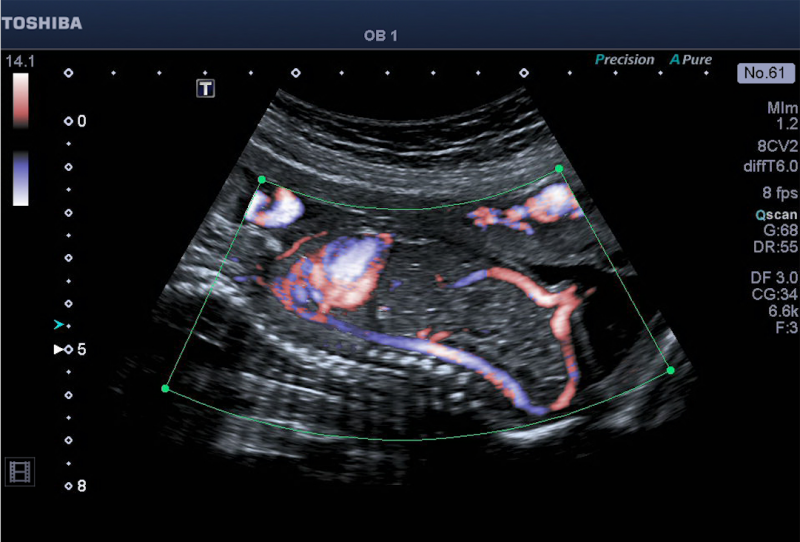

Below is a collection of prenatal ultrasound pictures from the Imaging Technology News (ITN) archive. Use the arrows to click through the image gallery. It includes transvaginal ultrasound images and fetal echocardiogram images. Fetal imaging is referred to by many names, including pregnancy sonograms, pregnancy ultrasound, endovaginal ultrasound, obstetric ultrasound, OB ultrasound, baby ultrasound, prenatal ultrasound. Fetal heart ultrasound is also called baby echo or prenatal echo.